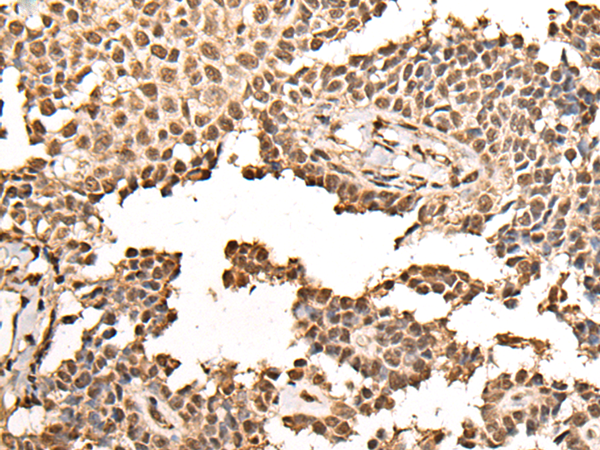

IHC positive control: |

Human ovarian cancer and human thyroid cancer |